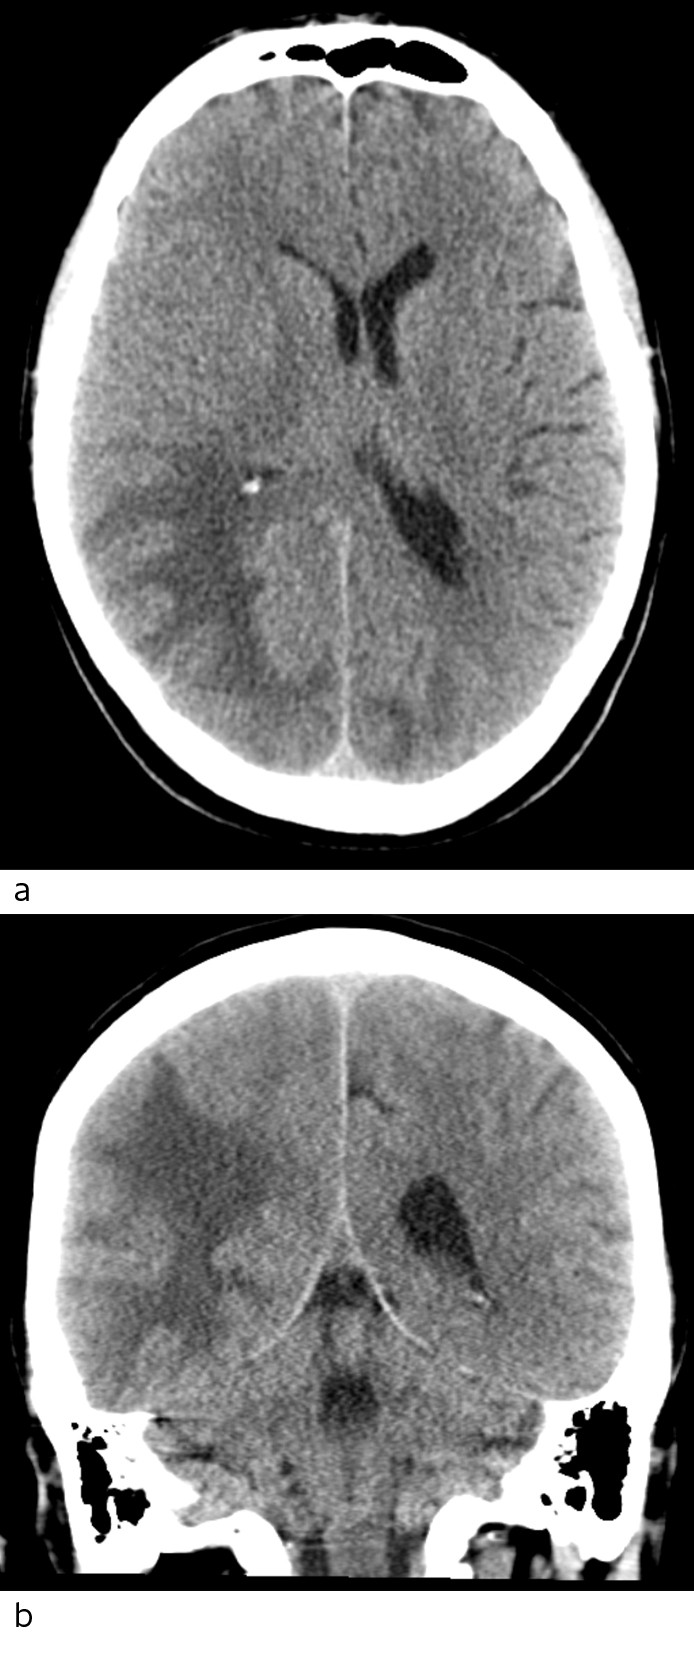

Regorafenib og kortikosteroidbehandling ble seponert, og pasienten opplevde spontan og rask bedring med tilbakegang av hodepine, normalisering av synsfelt, tempo og balanse uten ytterligere tiltak. Ved poliklinisk kontroll en måned senere hadde han full restitusjon av sine nevrologiske symptomer, med normal klinisk status. MR caput viste betydelig tilbakegang av lesjonene. CT caput tatt etter tre måneder viste fortsatt beskjedne restforandringer rundt bakre horn av høyre sideventrikkel og tilbakegang av midtlinjeforskyvning. Pasienten syntes da han hadde noe mer vansker med hukommelsen, og klinisk, biokjemisk og radiologisk var det tegn til progrediering av kreftsykdommen. Han døde av kreftsykdom tre måneder senere.

Radiologisk er syndromet preget av karakteristiske funn med ødem i hvit substans, oftest i bakre (parieto-oksipitale) deler av hjernen (5). I motsetning til bilaterale bakre infarkter, er oftest calcarine og paramediane deler av oksipitallappen uten ødem. MR spiller en viktig diagnostisk rolle (8), da lesjonene har økt signal på MR-bilder med T2-vekting og FLAIR-kontrast. Vanligvis har disse lesjonene en høy ADC-verdi på diffusjonssekvensen, en indikator på vasogent ødem og dermed reversibilitet og bedre prognose (9, 10). Bruk av suceptibilitetsvektede sekvenser (SWI, en forholdsvis ny metode) har vist at mikroblødninger er vanlig i affiserte områder hos pasienter med posterior reversibel encefalopati-syndrom, hovedsakelig i cortex, men også i hvit substans (8).